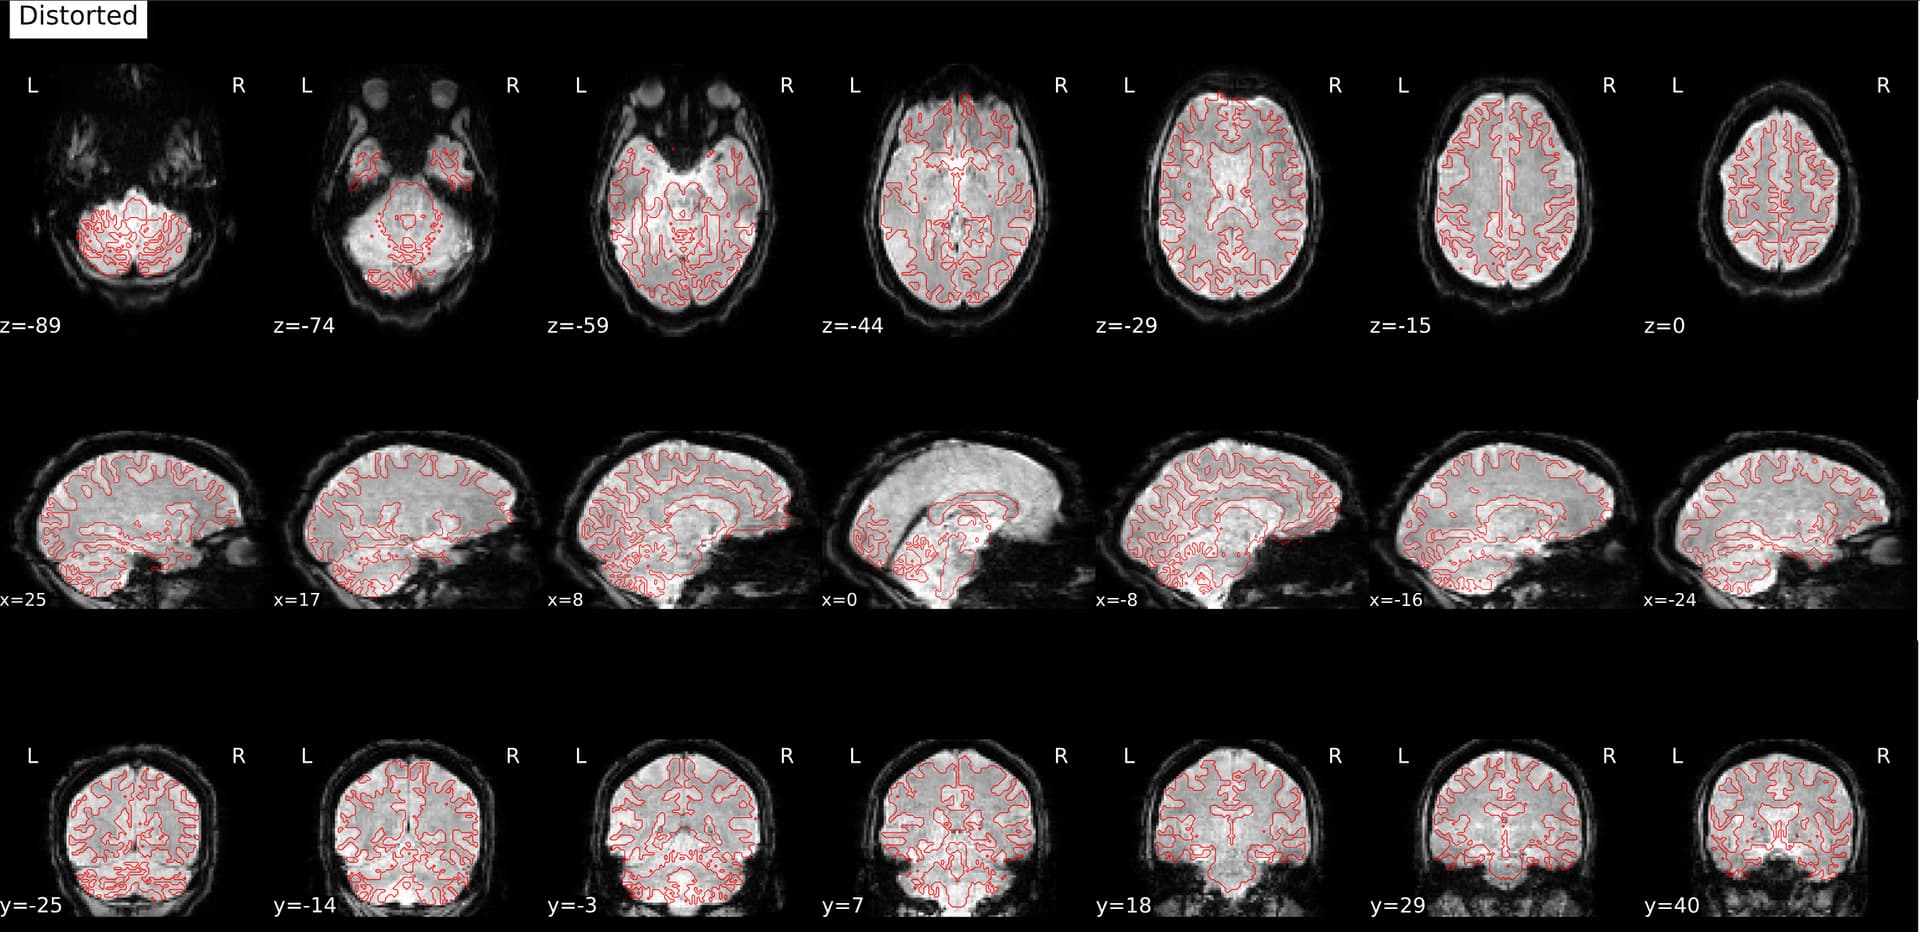

This is what the distorted version looks like, before SDC: